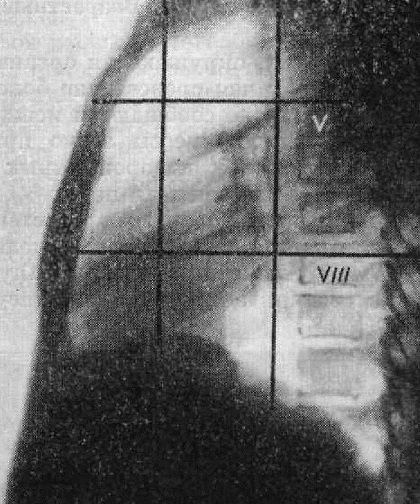

Thwining (1939) предложил еще более детальное деление средостенияна 9 частей. Это схематическое деление достигают путем проведения двух вертикальных линий во фронтальной и двух - горизонтальной плоскостях (рис. 231).

Границу между передним и средним средостением проводят по вертикальной линии, соединяющей грудино-ключичный сустав и передний отдел диафрагмы месте его проекционного пересечения с пле рой косой щели. Заднее средостение отделяется от среднего фронтальной плоскостью, проходящей несколько кзади от трахеи. Разграничительная линия между верхним и средним средостением проходит горизонтальной плоскости на уровне тела V грудного позвонка, а между средним и нижним - по горизонтали, проводимой на уровне тела VIII или IX грудного позвонка.

- Верхний - выше уровня V грудного позвонка

- Средний - располагается на уровне от V грудного позвонка (находится примерно на уровне бифуркации трахеи) до VIII грудного позвонка

- Нижний - ниже уровня VIII грудного позвонка